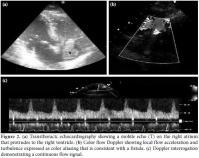

A 29-year-old male patient with BD was admitted to our clinic with dyspnea, palpitations, and chest pain. The diagnosis had been established three years earlier on the basis of mucocutaneous lesions and gastrointestinal disorders. The patient had then been treated with colchicine and corticosteroids. His past medical history also included deep venous thrombosis (DVT) in his calf. On his physical examination, a left parasternal murmur resembling the sound of a machine was detected along with abdominal ascites. His electrocardiography (ECG) and chest X-ray results were normal. Post-contrast thoracic computed tomography (CT) revealed right pulmonary effusion and decreased calibration together with a filling defect of the left inferior pulmonary artery due to a chronic PE (Figure 1a). On the abdominal ultrasononography, hepatic venous thrombosis was detected. The portal venous system was patent, but no enhancement was detected in the hepatic veins or proximal inferior vena cava (IVA) on the abdominal CT. The findings were concordant with BCS (Figure 1a). Two-dimensional transthoracic echocardiography revealed a mass on the right atrium protruding into the right ventricle (Figure 2a). The suprasternal view showed a turbulent and abnormal flow surrounding the arcus aorta and pulmonary artery (Figure 2b). Doppler interrogation demonstrated a continuous flow signal at that location. In addition, coronary angiography was performed to evaluate coronary involvement because of intractable angina pectoris, and a coronary arteryto- pulmonary artery fistula was detected arising from the left coronary artery (LCA) (Figure 3). On cardiac catheterization and oximetry study, there was a 5% step-up between the right ventricle and distal pulmonary artery, and the left-to-right shunt was 1.3. Since there was no evidence of a significant shunt, the fistula was not thought to be the cause of the angina, and the patient did not undergo corrective intervention. During the sixth month of treatment with colchicine, methylprednisolone, cyclophosphamide, and heparin, thoracic CT revealed complete lysis of the pulmonary thrombosis and ICT.